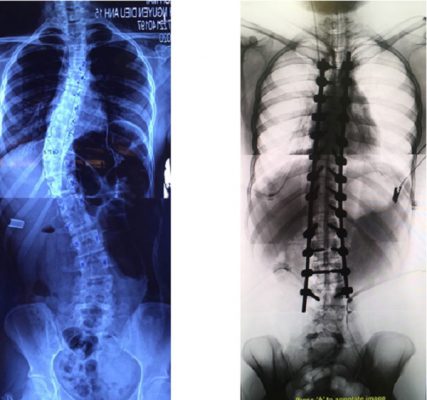

Vẹo cột sống là tình trạng cột sống bị cong một bên ở vùng ngực hoặc thắt lưng tạo hình chữ C, nếu bị cong cả ở ngực và thắt lưng có thể tạo hình chữ S.

3. Phẫu thuật vẹo cột sống như thế nào?

Tuỳ thuộc vào loại vẹo, mức độ vẹo và nguyên nhân gây Vẹo cột sống mà các phương án mổ có thể khác nhau.

Đường phẫu thuật phía sau: với cá trường hợp góc vẹo > 40º, có thể sử dụng trong tất cả cá trường hợp vẹo cột sống vô căn, là đường mổ ưu tiên cho vẹo cột sống ngực và cốt sống kép

Phẫu thuật 2 đường mổ trước và sau: Áp dụng với các trường hợp góc vẹo > 75º, sự linh hoạt của cột sống không còn. Do đó cần loại bỏ sụ liên kết giữa các đốt sống vẹo để nắn chỉnh vẹo.